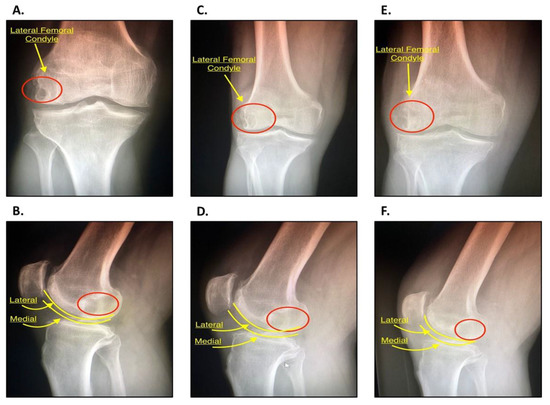

Intraosseous Bioplasty for a Subchondral Cyst in the Lateral Condyle of Femur

2.2. History and Diagnosis